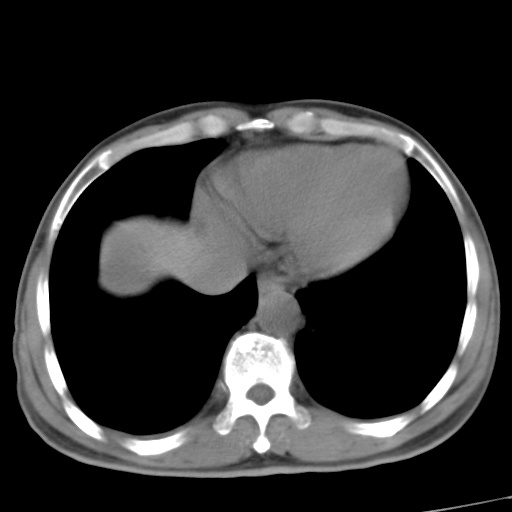

肝脏多发类圆形低密度影,考虑肝脏转移瘤,肝胃韧带一淋巴结肿大,原发?胃癌?

考虑胃癌肝脏转移可能性大。

考虑胃癌并肝脏及腹膜后淋巴结转移;不排除淋巴瘤。

肝内转移瘤,腹腔及腹膜后淋巴结转移。